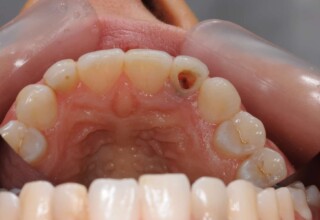

Posterior Tooth Root Canal Restoration with a Composite Resin Filling

The common restoration of a posterior tooth after a root canal is a crown. Its main purpose is to protect from fracture and concomitant extraction. In very few cases that specific criteria (mainly remaining tooth structure) are met or where finances predominate, an extensive composite filling can restore both aesthetics and function.